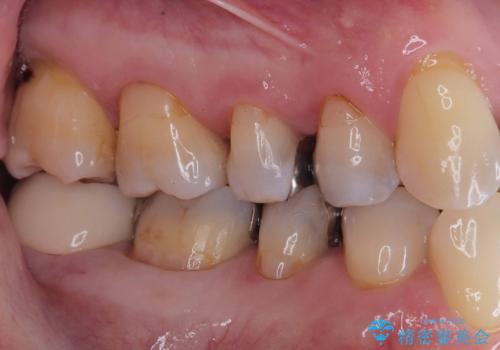

銀歯を外し虫歯を除去後、オールセラミッククラウンで治療を行いました。

当院は適合にこだわったセラッミク治療を行っているので、虫歯の再発のリスクを大きく下げる事が可能です。